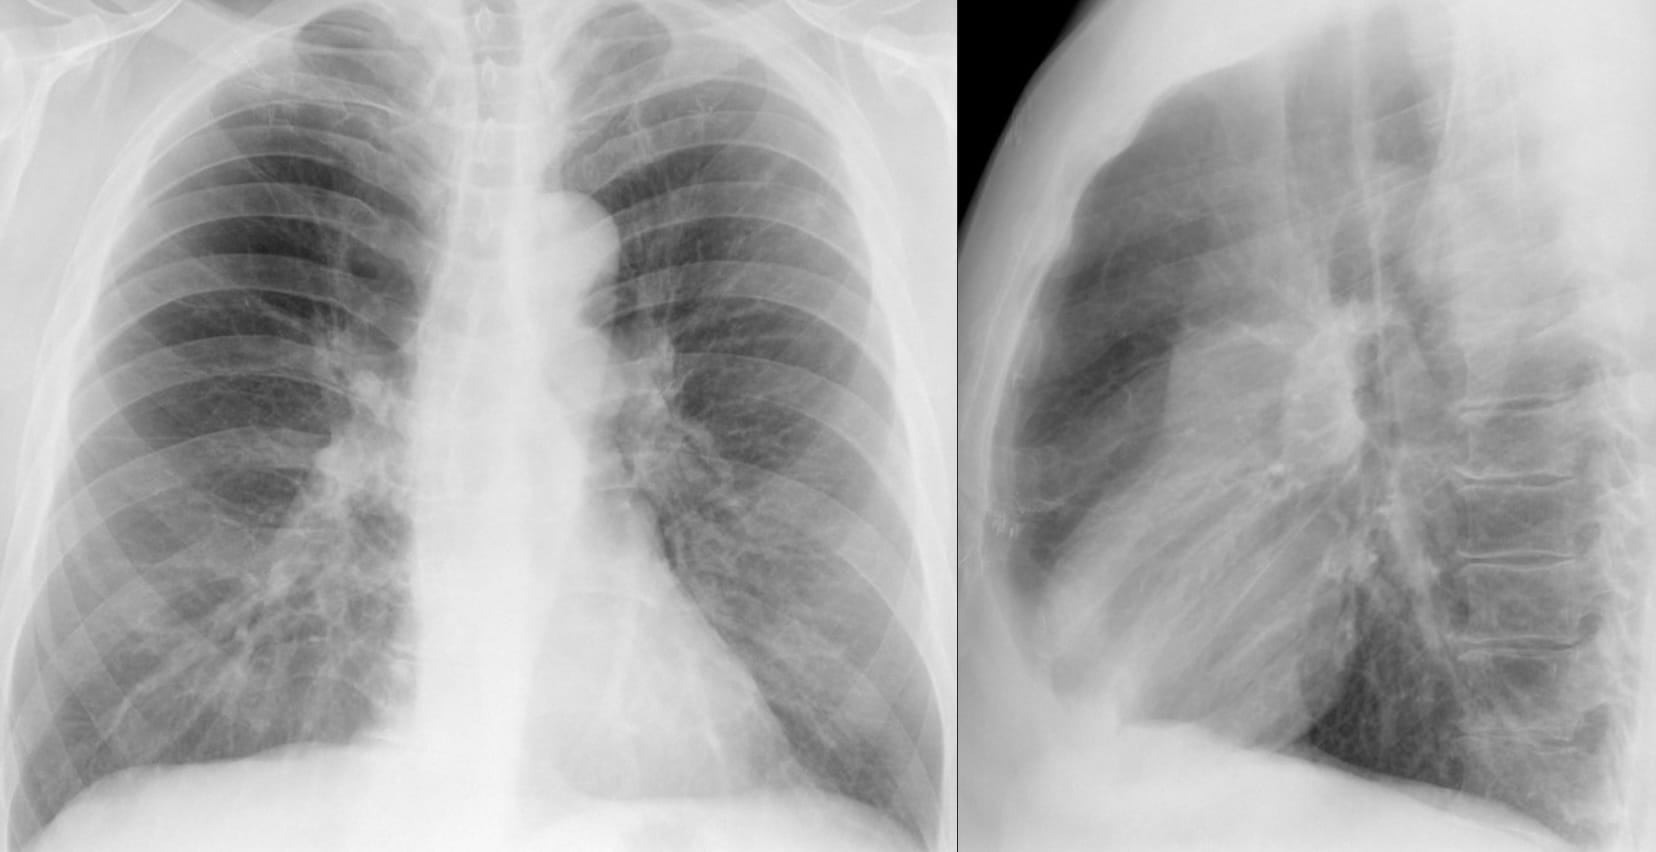

Another Aunt Minnie

“The cysts’ diameters in AEF are significantly larger than those in UIP and NSIP, but, at the same time, the walls are significantly thinner than those of UIP and thicker than those of centrilobular emphysema (CLE)”

Examples from the article:

One observation seems relevant: the cystic spaces may be situated away from the pleural surface.